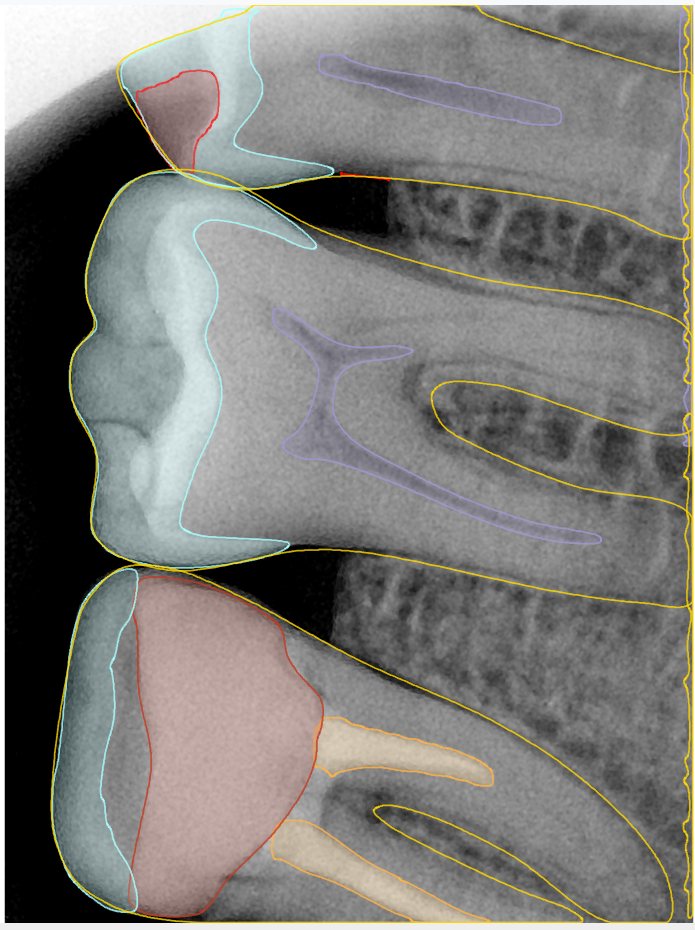

第二版算法问题测试

| 第一版 | 第二版 | 是否解决 | |

|---|---|---|---|

![]() | ![]() ![]() 边角识别有问题 龋齿识别不全 牙髓识别不全 | ![]() | 解决 |

![]() | ![]() 边角识别有问题 识别信息有误 自查(牙冠识别不全) | ![]() | 解决 |

![]() | ![]() ![]() 边角识别有误 大范围填充识别遗漏 | ![]() | 解决 |

![]() | ![]() 识别信息不全 | ![]() | 解决 |

![]() | ![]() ![]() 边角问题 牙胶识别不全 牙冠识别不全 | ![]() | 解决 |

![]() 换图片 | ![]() | ![]() 牙冠部分稍微白了一些就识别成小范围修补,部分判断异常 | 部分解决,修复类略敏感,牙冠部分稍微白了一些就识别成小范围修补,部分判断异常。 |

![]() | ![]() ![]() 牙冠识别不全 牙髓不全 根尖炎龋齿识别有误 | ![]() | 解决 |

![]() | ![]() | ![]() | 解决 |

![]() 换图片 | ![]() | ![]() | 解决 |

![]() | ![]() 牙冠识别有误 | ![]() | 解决 |

![]() 换图片 | ![]() ![]() 边角识别有误 | ![]() 修复类敏感 | 部分解决,图像过白,导致修复类判断异常。 |

![]() 换图片 | ![]() 牙冠识别不全 | ![]() 修复类敏感 | 部分解决,图像过白,导致修复类判断异常 |

结论:修复类出现了不鲁棒的情况,后续需要加入轮廓的扩充数据进行增强。